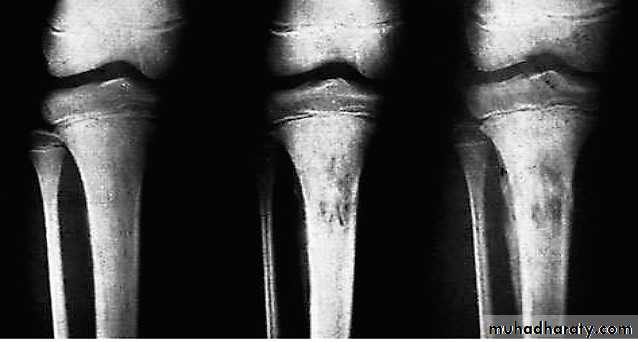

It is common around the knee jointProximal tibia and lower femur

50% around knee

Radiography

* Early is negative only soft tissue swelling.* After 2 weeks will shows rarefaction of the bone

* After 3 weeks new bone formation ( periosteal new bone formation )( involucrum)